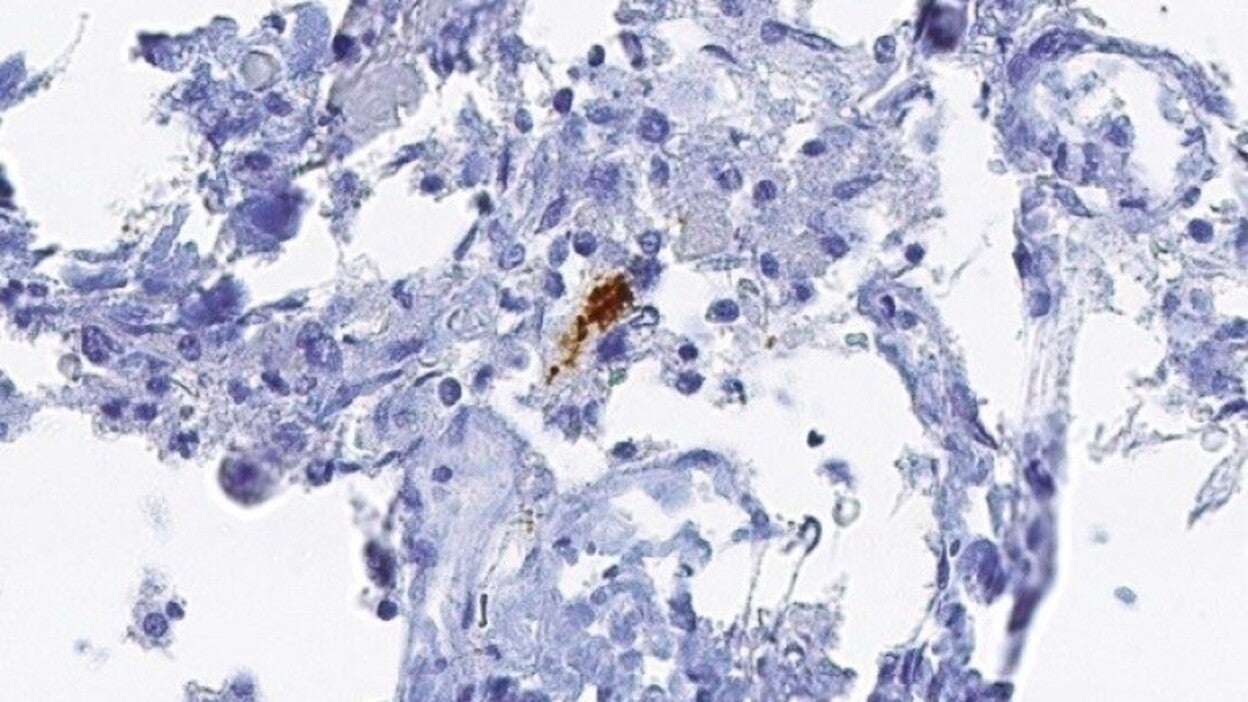

En este sentido, el estudio ha descrito un evento clave en el proceso de necroptosis que es cuando RIPK1 y RIPK3 forman una estructura filamentosa conocida como necrosoma, la cual parece que da comienzo al proceso de necroptosis.

A continuación, identificaron la cascada molecular de la activación de necroptosis, con RIPK1 activando a RIPK3. Este complejo proteico se une y activa MLKL. Concretamente, el análisis de ARNm y proteína reveló niveles elevados tanto de RIPK1 como de MLKL en los tejidos cerebrales 'post mortem' de pacientes con Alzheimer, en comparación con los cerebros 'post mortem' normales.